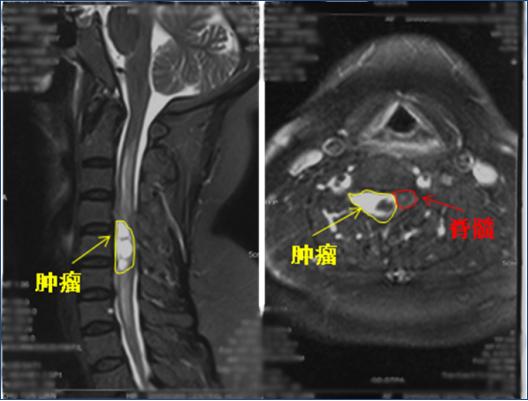

61岁的朱女士来自山东单县,入院半年前突然出现右侧颈肩部疼痛麻木,在当地医院反复就诊,先后诊断为“肩周炎、颈椎病”,曾尝试多种保守治疗方法,症状依然进行性加重。入院前一个月患者出现右上肢疼痛麻木,肌肉力量降落,吃饭、穿衣、睡觉等日常生活均受到严重影响,经颈椎磁共振检查发现其颈4—6水平椎管内有一个巨大肿瘤。

剥离过程轻巧准确,只见,位于颈4-6脊髓右腹侧的肿瘤被神经缠绕着,颈5右侧神经根部分神经束穿行于肿瘤内,同时肿瘤对颈5神经根也造成了严重压迫。程钢戈主任在显微镜下,一点点剥离显露肿瘤,一丝丝清除薄如蝉翼的脊髓粘连,直到将这一30×15×15毫米大小的肿瘤完整切除(如下图),丝毫未伤及任何神经组织。

紧接着,杜俊杰主任带领骨科医生团队再次上阵,为患者完美重建了颈椎的稳定性。两科室密切配合,历时4个小时,圆满完成这一高难度、高风险的颈椎椎管内巨大肿瘤切除术。术后当天晚上,折磨了患者大半年的术前症状完全消失,由于疼痛已经1个月没法入睡的朱女士终于睡了一个安稳觉。术后12小时,患者就从ICU转回普通病房;术后仅5天,患者就能下地活动,右上肢肌力也完全恢复正常。术后病理回报此肿瘤为神经鞘瘤。